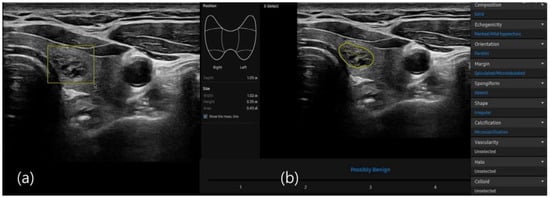

2.4. S-Detect